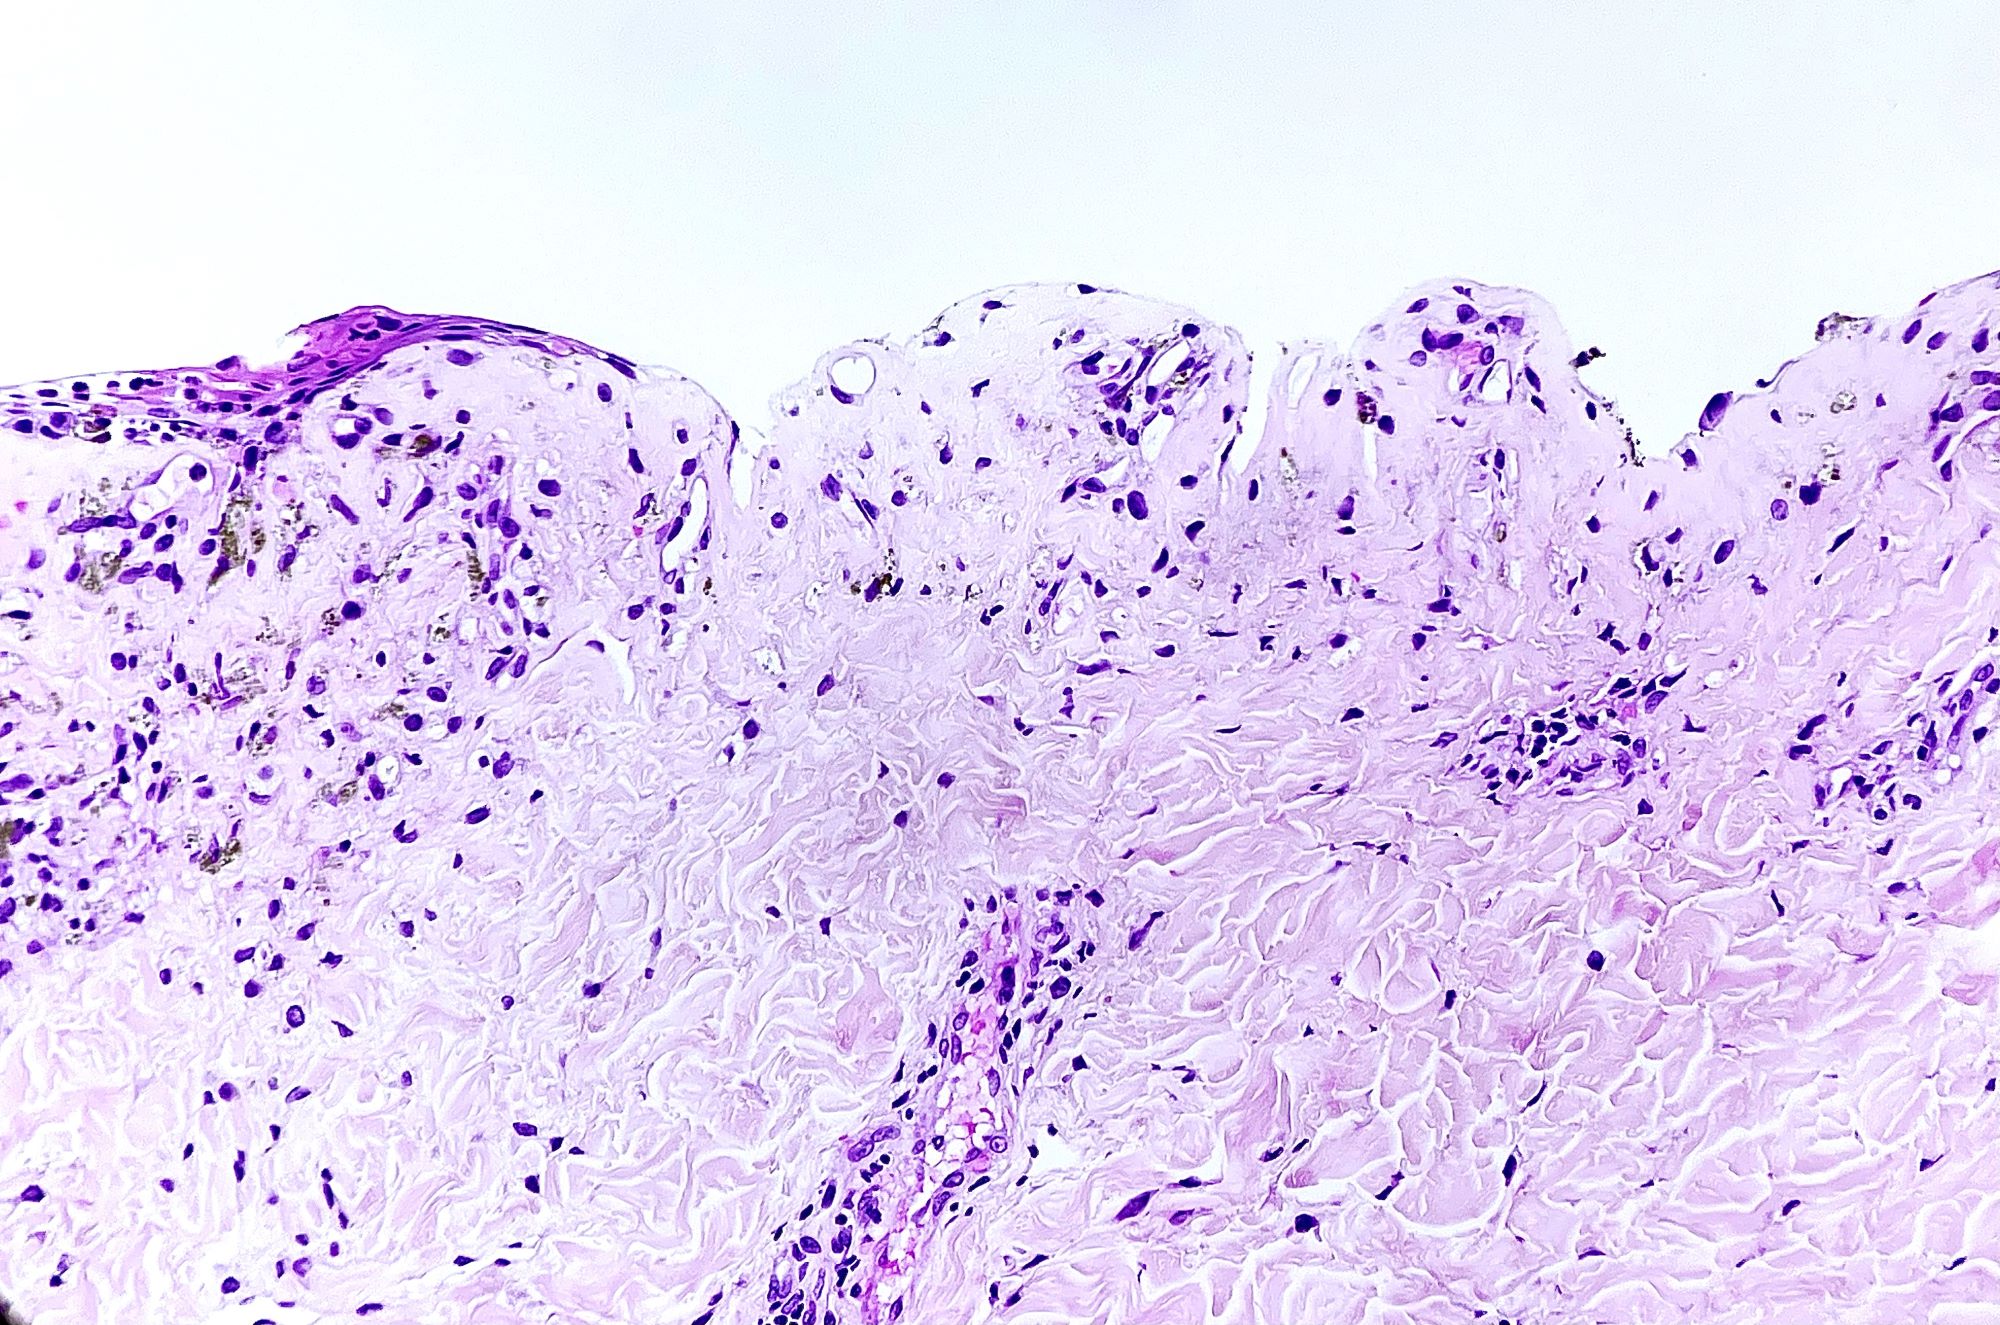

Microscopic (histologic) description

- Acute GVHD (Patterson: Weedon's Skin Pathology, 4th Edition, 2015)

- Mild to moderate superficial perivascular lymphocytic infiltrate with exocytosis of inflammatory cells into the epidermis and basal vacuolation, interface dermatitis

- Scattered, shrunken, eosinophilic keratinocytes with pyknotic nuclei, at all levels of the epidermis; often accompanied by 2 or more lymphocytes, producing the satellite cell necrosis - lymphocyte associated apoptosis

- Occasionally, rare eosinophils can be present; melanin incontinence is prominent in patients with darker skin types

- If severe, subepidermal microvesicles, subepidermal blisters and epidermal necrosis

- Lymphocytic infiltrate in GVHD after solid organ transplantation is usually brisk in comparison to the sparser inflammation following bone marrow transplantation

Microscopic (histologic) images

Contributed by Silvija P. Gottesman, M.D. and Ohoud Aljarbou, M.D.